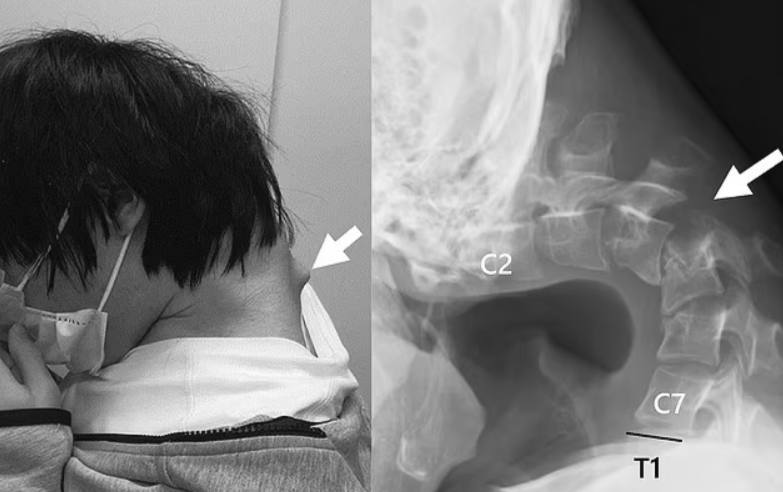

Хроническое сгибание головы вперед вызвало формирование заметной костной шишки на затылке — так называемого «ушного нароста», который ранее считался редкостью, но сейчас встречается всё чаще среди молодых пользователей гаджетов.

После полного обследования врачи поставили диагноз: выраженная деформация шейного отдела позвоночника, требующая немедленного хирургического вмешательства. Консервативные методы лечения, такие как физиотерапия, ЛФК и медикаменты, не принесли результата.